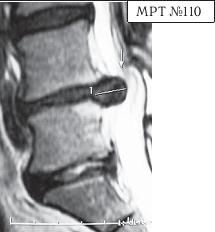

Случаи послеоперационных рецидивов грыж межпозвонкового диска бывают разные, но причины, как правило, идентичны. Вот одна из типичных ситуаций. Врачи во главе с хирургом после хирургической операции пациента по поводу грыжи межпозвонкового диска в сегменте LV-SI в качестве профилактики посоветовали ему заниматься вытяжением позвоночника под собственным весом и укреплением мышечного корсета путём выполнения специальных упражнений на наклонной плоскости. Результат усердия пациента, последовавшего такому совету, можно наблюдать на МРТ № 110 (см. стр. 286).

Исходя из анатомического и физиологического строения позвоночника человека и неизбежного действия законов физики, результат от такой «профилактики» вполне прогнозируем. Поэтому логично предположить, что врачи, посоветовавшие данному пациенту такую «профилактику», спровоцировавшую секвестрированную грыжу межпозвонкового диска в сегменте L^ — Ly, просто не знали о её последствиях. Если бы здоровье пациента позволило бы продолжить эти упражнения, то аналогичные осложнения неизбежно образовались бы и в вышележащих позвоночнодвигательных сегментах.

На МРТ № 110 наблюдается состояние поясничного отдела позвоночника: секвестрированная грыжа межпозвонкового диска в сегменте LIV-LV с разрывом задней продольной связки, абсолютный стеноз спинномозгового канала.